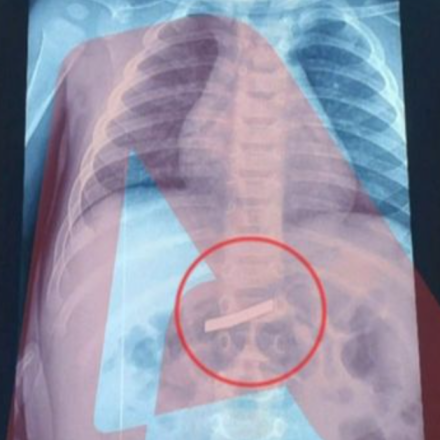

Αφού προσδιορίστηκε το ακριβές σημείο που βρισκόταν το ξυράφι, το τρίχρονο παιδάκι υποβλήθηκε σε χειρουργική επέμβαση για την αφαίρεσή του.